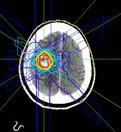

転移性脳腫瘍に対する定位放射線治療例です。

中左図:治療計画です。多方向から腫瘍に照射します。

中右図:線量分布図です。腫瘍部分に線量が集中しているのがわかります。